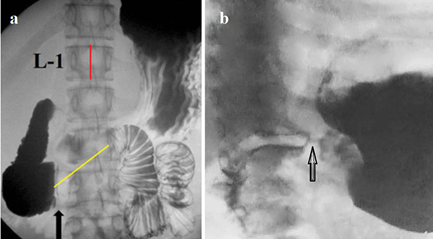

Figure 5 Evacuation of gastric contents into the small intestine. (a) Such cases are described as superior mesenteric artery (SMA) syndrome. The black arrow shows the beginning of compression of the duodenum. However, this compression cannot be caused by the SMA, since this vessel is in the midline of the vertebra. Secondly, with the diameter of the aorta ≈ 2 cm and the SMA ≈ 1 cm, the compression of the intestine cannot be more than 2 cm. Since the height of L-1 is 2.2 cm, the length of the narrowed section in the 3rd part of the duodenum (yellow line) is 4 cm, which corresponds to the location and length of Ochsner's sphincter. This radiograph is also presented here to show the rapid evacuation of gas and barium into the jejunum in a horizontal position. (b) In the infant's upright position, the gas entered the duodenum. The arrow indicates the pyloric sphincter.